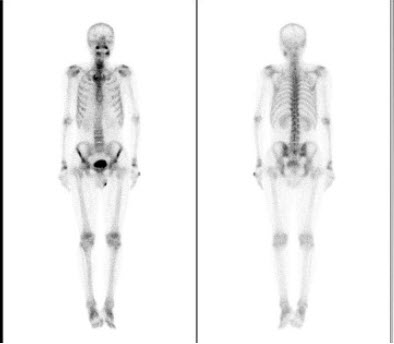

男性,48岁,血象示三系减少,双侧下肢疼痛,既往有鼻咽癌病史,行全身骨显像如图,最可能的诊断是()

A.双侧肱骨、股骨转移癌